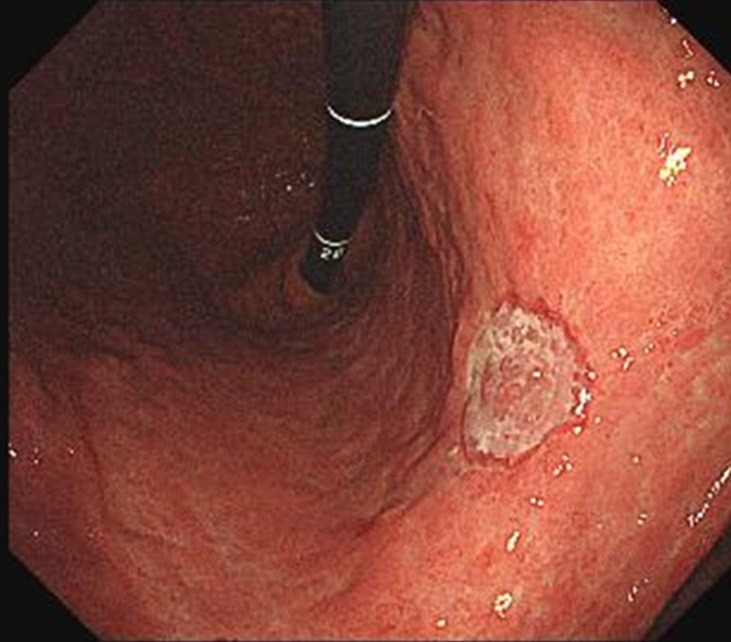

용종 및 선종 감별

위 용종은 대부분 양성이지만, 다음과 같은 경우 조직검사가 필요합니다:

- 크기가 1cm 이상

- 모양이 넓적하거나 불규칙

- 표면이 거칠고 홍반을 동반

- 선종이 의심되는 경우

선종은 훗날 암으로 진행할 수 있기 때문에 내시경 절제술 등을 검토하기 위해 조기 평가가 필요합니다.